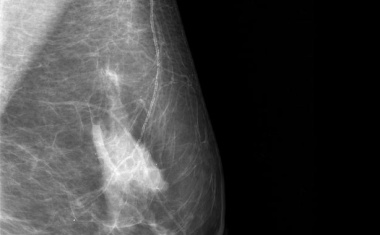

Brustkrebsvorsorge: KI verbessert Diagnose

28.06.2022 -

Wenn Künstliche Intelligenz (KI) zusammen mit Radiologen eingesetzt wird, können in der Brustkrebsvorsorge bessere Ergebnisse erzielt werden, als wenn jede Seite allein...